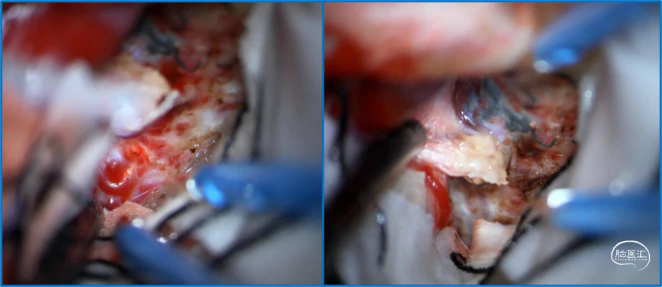

典型病例

![]()

稳妥的外科治疗方案:先介入栓塞颈外动脉的供血动脉,然后显微手术切断颈内动脉的供血动脉,阻断引流静脉,电凝封闭硬膜瘘口。

神经内镜可以辅助确认颞极深部的引流静脉,避免残留引流静脉。